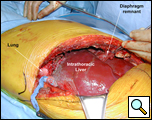

Through a 7th interspace right thoracoabdominal incision, the right lung was decorticated and pneumolysis performed (Figure 5). Once dissection was complete, the liver was found in the pleural space with only a small rim of diaphragm medially (Figure 6). The liver was completely mobilized and reduced into the abdomen, insuring that the right hepatic vein was not kinked. Multiple liver biopsies were obtained. The diaphragm was reconstructed using a 15x25cm 2mm thick polytetrafluoroethylene patch, anchoring it posteriorly near the 10-11th thoracic vertebral level to the posterior mediastinal fascia, laterally around the ribs, and anteriorly to the medial remnant of the diaphragm (Figure 7).